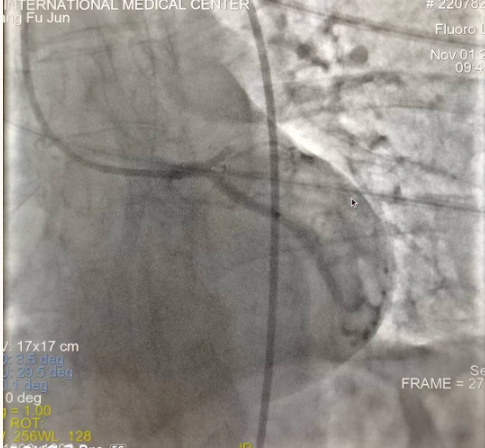

閉塞的血管再通時(shí)間取決于急救時(shí)長(zhǎng)、轉(zhuǎn)運(yùn)時(shí)長(zhǎng)和治療時(shí)長(zhǎng),在前兩方面,醫(yī)院已為患者爭(zhēng)取了最短時(shí)間?;颊呒覍龠h(yuǎn)在陜北,雖然已在趕來(lái)的路上,但最快抵達(dá)西安也要3小時(shí),在與患者家屬電話溝通同意急診手術(shù)后,醫(yī)療總值班代家屬簽字,康曉軍在請(qǐng)示心臟病醫(yī)院王海昌院長(zhǎng)及心臟內(nèi)科CCU尚福軍主任后,積極進(jìn)行術(shù)前準(zhǔn)備。在沒(méi)有家屬陪同、沒(méi)有交費(fèi)、沒(méi)有辦入院手續(xù)的情況下,患者經(jīng)胸痛中心綠色通道被送往心臟冠脈介入手術(shù)室,打通了完全閉塞的心臟前降支近段血管。